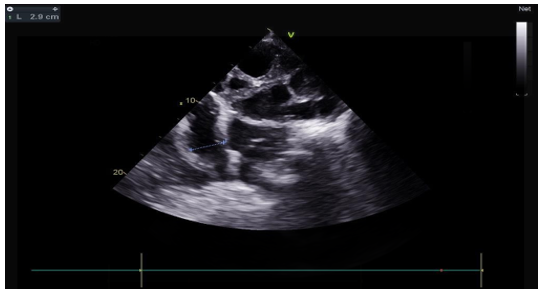

The transthoracic echocardiographic examination revealed (Figures 8 – 18):

- A lobulatedcystic image exerting severe compression on both the right and left cardiac chambers, resulting in hemodynamic disturbance and considerable fluctuation in respiratory flows (Figures 12 – 13,17).

- Left ventricule showed no sign of dilatation. Al though the assessment of contractile function was influeced by compressio from pulmonary hydatid cyst, it appears to maintain functionnality.

- Elevated left ventricular filling pressure were noted.

- The right ventricle exhibited no dilation (Figure 11) despite the presence of longitudinal systolicdys functio n (Figures 14).

- Grade II tricuspid insufficiency was identified, with an estimated systolic pulmonary arterial pressure of 47 mmHg (calculated as 37 + 10 mmHg), indicating the presence of pulmonary hypertension.

- The inferior vena cavademonstrated no dilation (Figure 18) and wasnoted to be non-compliant (Figure 16).

- No pericardial effusion was present.